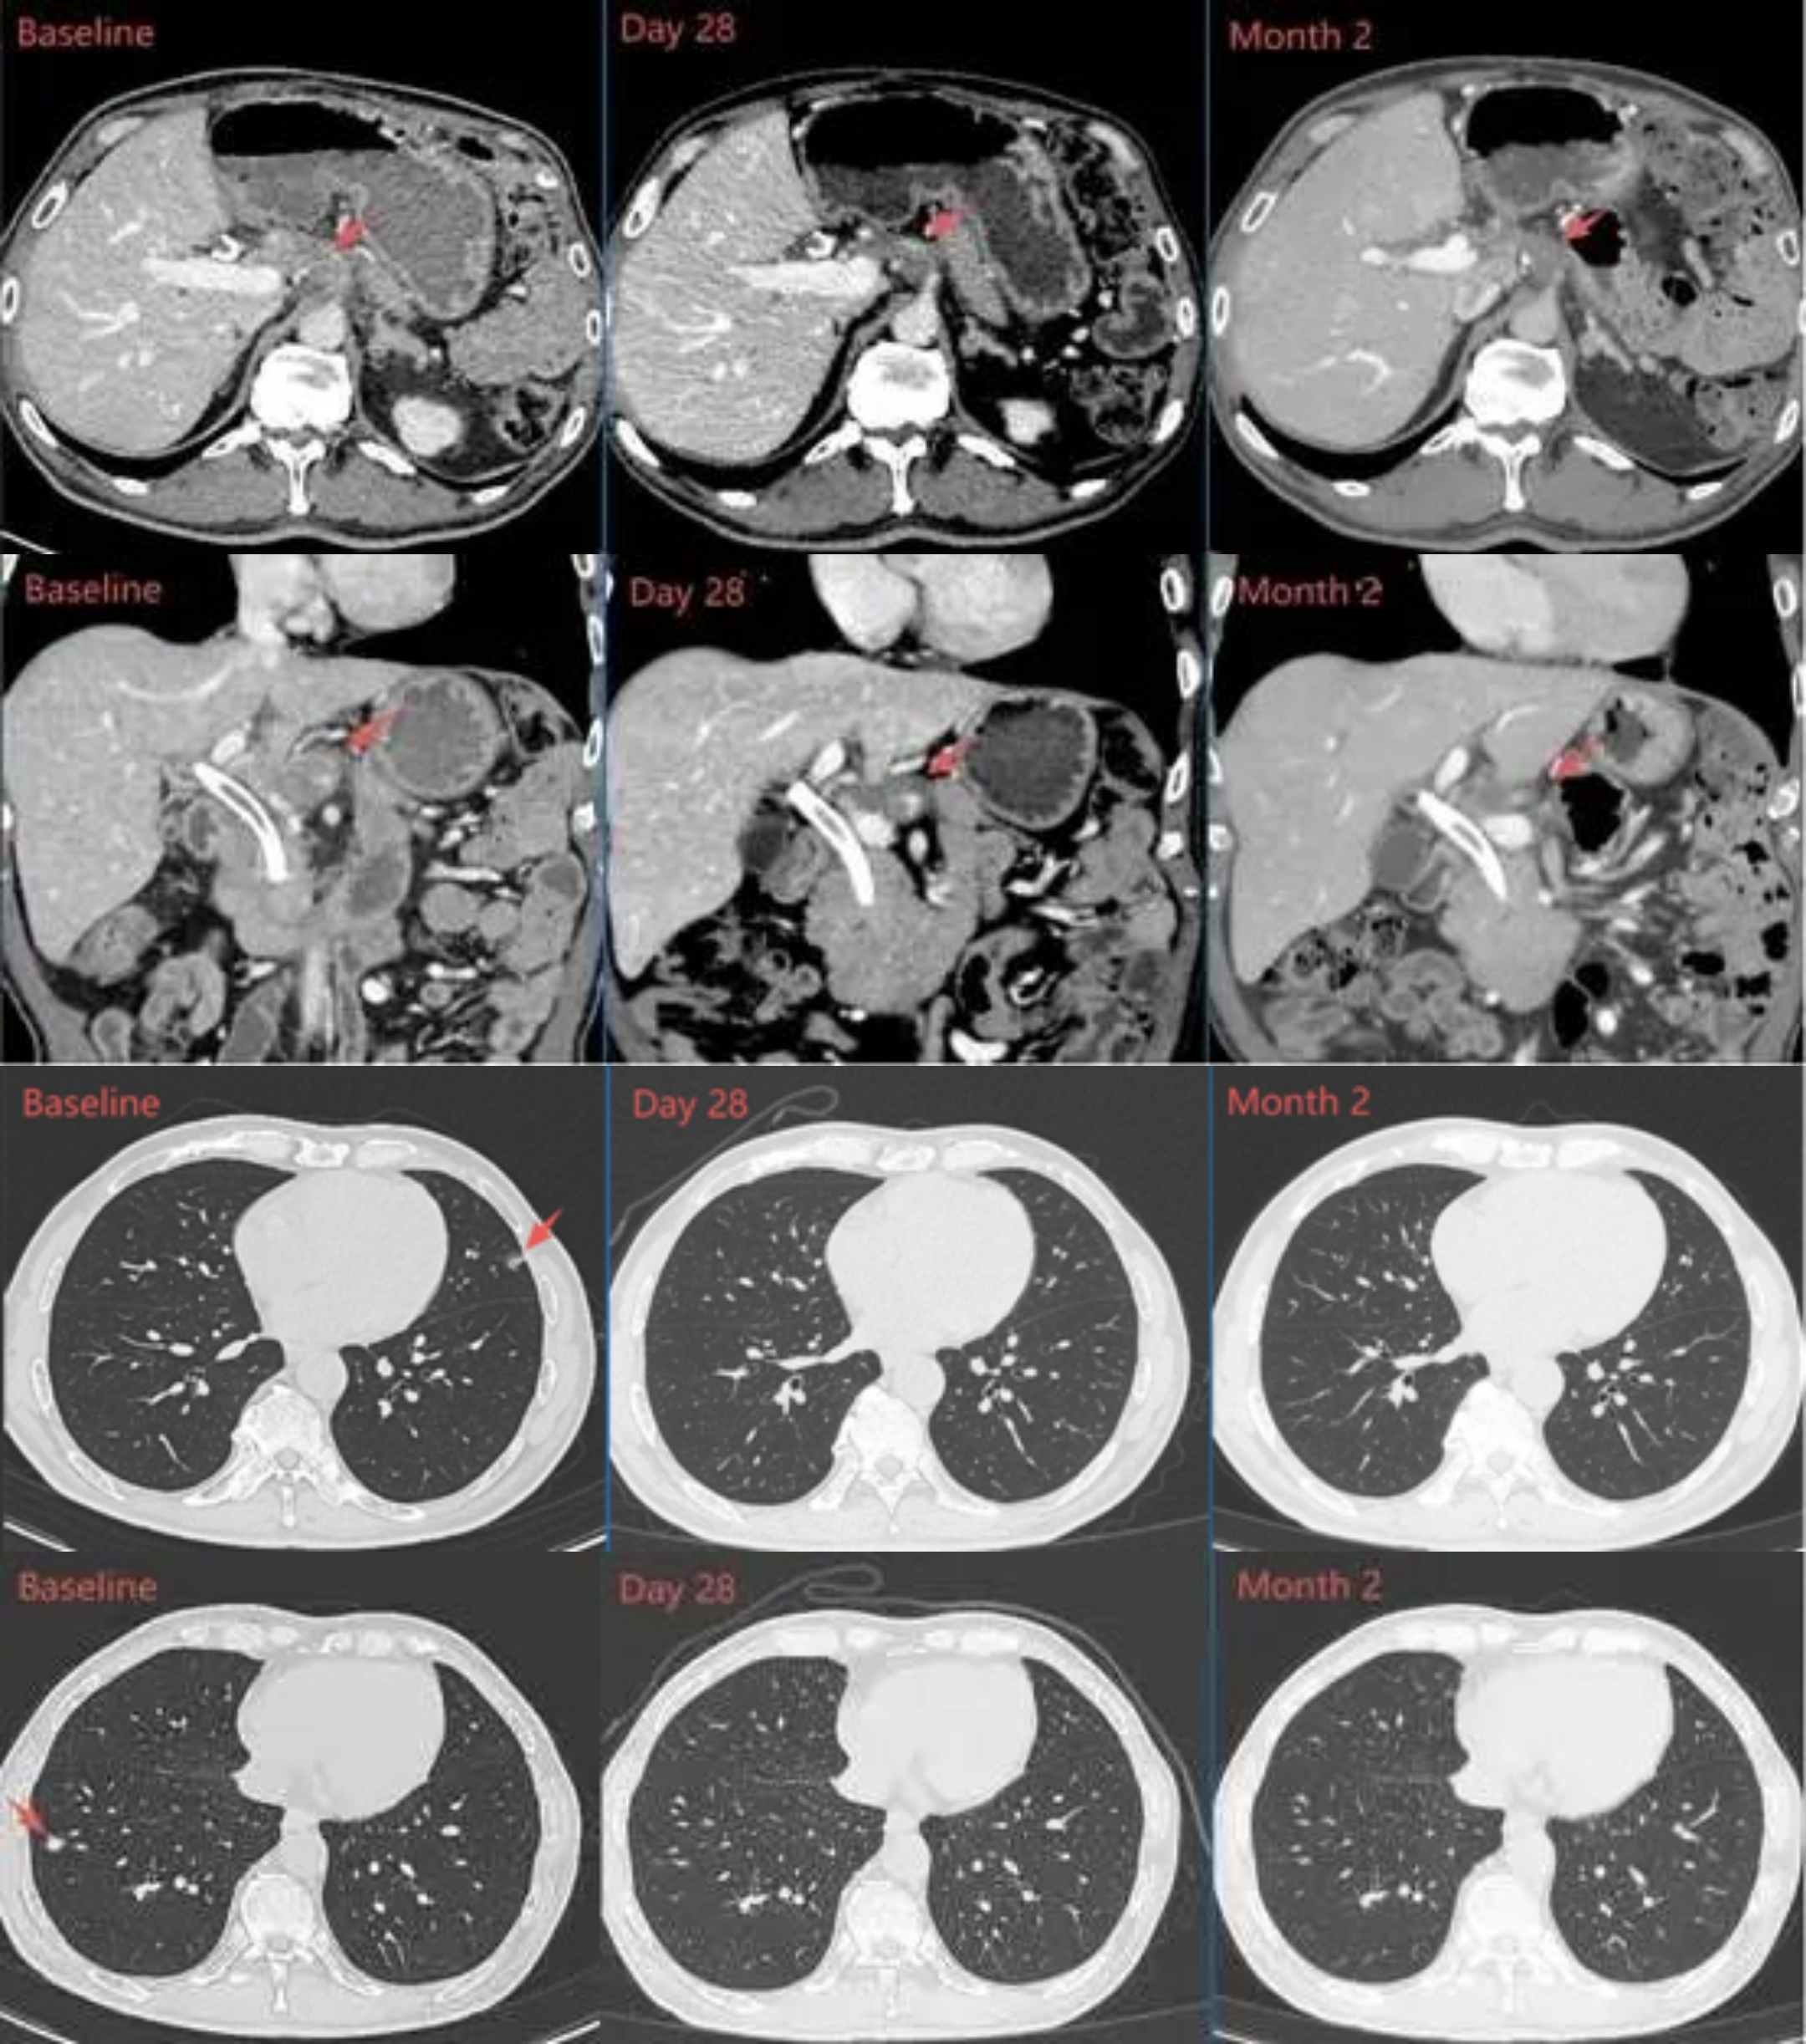

74岁的胰腺癌患者在经历20多次化疗后,肿瘤仍持续进展。当他几乎耗尽所有治疗选择时,一项名为TCR-T的新兴免疫细胞疗法带来了转机。 单次细胞回输28天后,复查结果显示:患者肝脏上的三个靶病灶明显缩小,肿瘤标志物CA19-9水平从758U/ml降至78U/ml,降幅近90%,且治疗安全性良好。